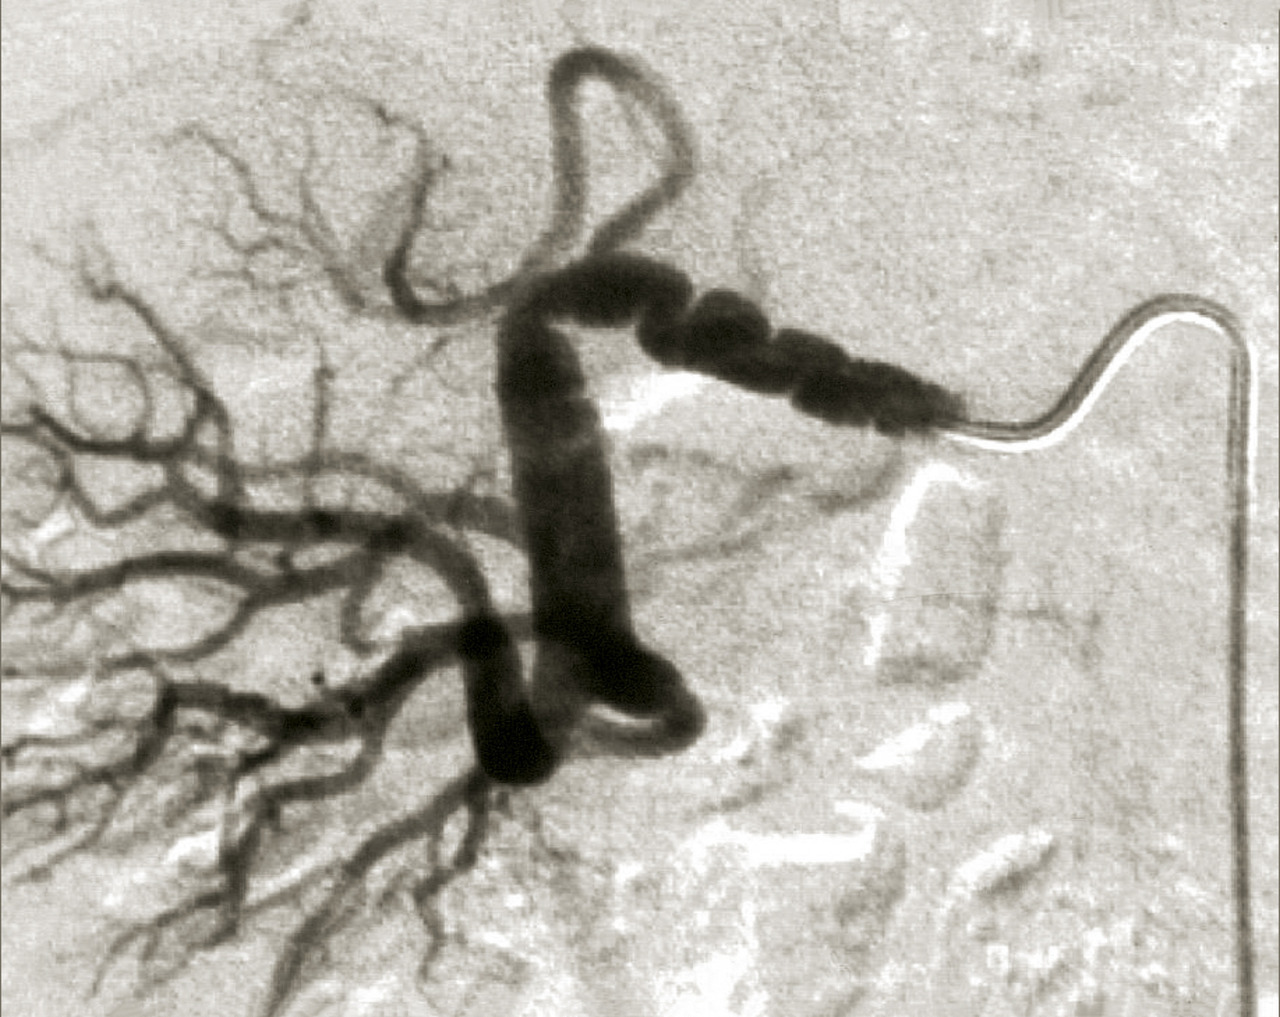

En cas de fibrodysplasie, les lésions sont multiples, distales, souvent bilatérales, avec aspect en « collier de perles » (fig. 4). Il est recommandé, dans cette pathologie qui est souvent multifocale, de rechercher d’autres lésions artérielles (sténoses ou anévrismes) au niveau des artères digestives, cervicales et intracrâniennes.